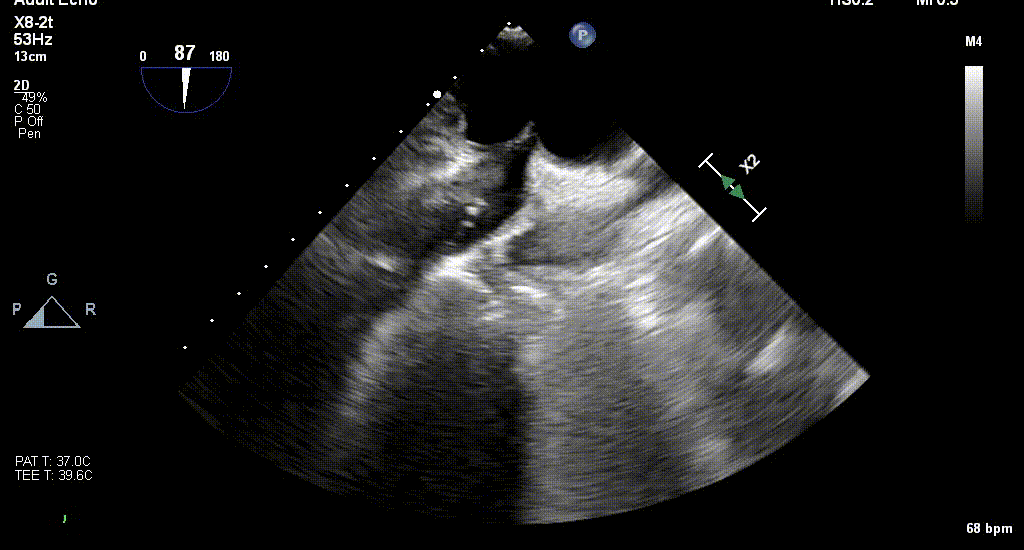

术前TEE评估

原发性MR,交界C1区脱垂,反流程度4+;二尖瓣瓣口面积3.88cm²,平均跨瓣压差2mmHg;二尖瓣前叶(A1)长度16.2mm,二尖瓣后叶长度(P1)长度9.9mm,脱垂高度6mm。